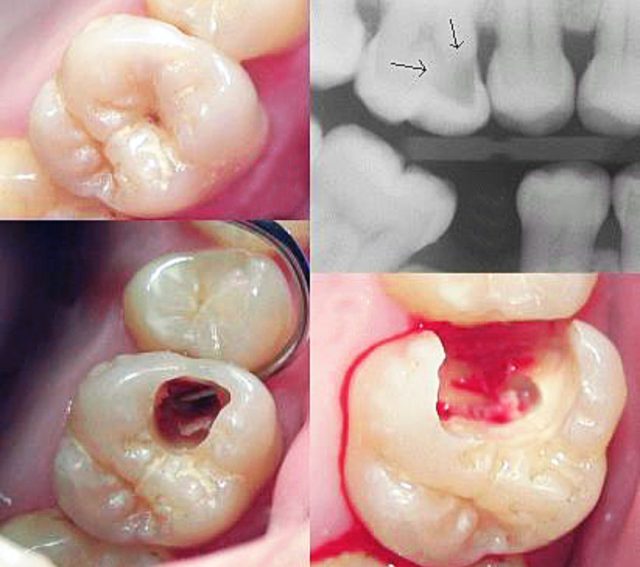

Karijes je demineralizacija i razaranje zubnih tkiva izazvano bakterijama u usnoj šupljini. Proces počinje na površini gleđi, a zatim se širi u dublje slojeve zuba. Ako se ne zaustavi, može zahvatiti pulpu i izazvati bol, infekciju pa čak i gubitak zuba.

- Rani stadijum: Bijele mrlje na gleđi, bez bola.

- Srednji stadijum: Tamne rupice, osjetljivost na hladno, toplo ili slatko.

- Napredni stadijum: Jak bol, otok, pa čak i gubitak zuba.

- Vizuelni pregled – otkrivanje promjena na površini zuba.

- Rendgenske snimke – otkrivanje karijesa između zuba ili ispod plombi.